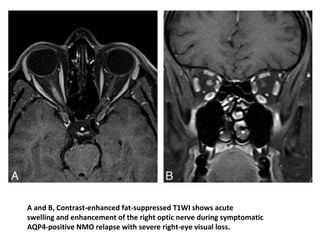

A and B, Contrast-enhanced fat-suppressed T1WI shows acute

swelling and enhancement of the right optic nerve during symptomatic

AQP4-positive NMO relapse with severe right-eye visual loss.